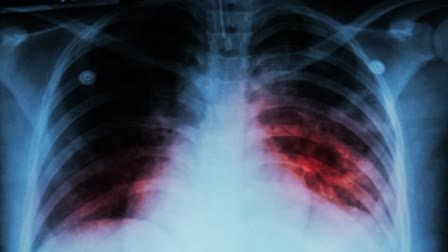

लखनऊ : किंग जार्ज चिकित्सा विश्वविद्यालय के रेस्पिरेटरी मेडिसिन विभाग के विभागाध्यक्ष डॉ. सूर्यकान्त का कहना है कि ‘टी.बी. मुक्त भारत’ प्रधानमंत्री का ड्रीम प्रोजेक्ट है, टीबी रोगियों के लिए बढ़ाये गये पोषण भत्ता से टी.बी. उन्मूलन कार्यक्रम को बल मिलेगा। उन्होंने कहा कि कुपोषण और टीबी एक सिक्के के दो पहलू हैं। कुपोषण से टीबी रोग के विकसित होने का जोखिम बढ़ता है, टीबी होने के कारण कमजोरी के साथ वजन घटता है। इससे कुपोषण की स्थिति और खराब हो जाती है। इसलिए टीबी रोगियों में कुपोषण को दूर करने से उपचार के प्रति प्रतिक्रिया बेहतर होगी, मृत्यु दर कम होगी और लम्बे चलने वाले उपचार के परिणाम बेहतर होंगे।

भारत सरकार ने इसी को ध्यान में रखते हुए 500 रुपये प्रतिमाह की जगह 1000 रुपये प्रतिमाह टीबी रोगियों का पोषण भत्ता कर दिया है। यह वृद्धि एक नवम्बर 2024 से प्रभावी होगी और सभी नए लाभार्थियों के साथ-साथ प्रभावी तिथि के बाद मिलने वाले लाभों पर भी लागू होगी। यह प्रोत्साहन 3,000 रुपये की दो बराबर किस्तों में दिया जाएगा, जिसमें 3,000 रुपये का पहला लाभ निदान के समय अग्रिम के रूप में दिया जाएगा और 3,000 रुपये का दूसरा लाभ उपचार के 84 दिन पूरे होने के बाद दिया जाएगा। जिन लाभार्थियों के उपचार की अवधि छह महीने से अधिक है, उन्हें 1,000 रुपये प्रति माह का नया लाभ दिया जाएगा। परिवार के सदस्यों में कुपोषण से संबंधित टीबी के प्रति संवेदनशीलता को दूर करने के लिए टीबी रोगियों, परिवार के सदस्यों (घरेलू संपर्क) को निक्षय मित्र पहल के अंतर्गत शामिल करना प्रधानमंत्री टीबी मुक्त भारत अभियान (पीएमटीबीएमबीए) को मंजूरी दी गई है। नए संक्रमणों को रोकना तथा टीबी से संबंधित मृत्यु दर को कम करना। उपरोक्त सभी उपायों से पोषण संबंधी सुधार में सहायता मिलने की उम्मीद है। भारत में टीबी के उपचार और परिणामों में सुधार तथा इसके कारण होने वाली मृत्यु दर में कमी लाना है।